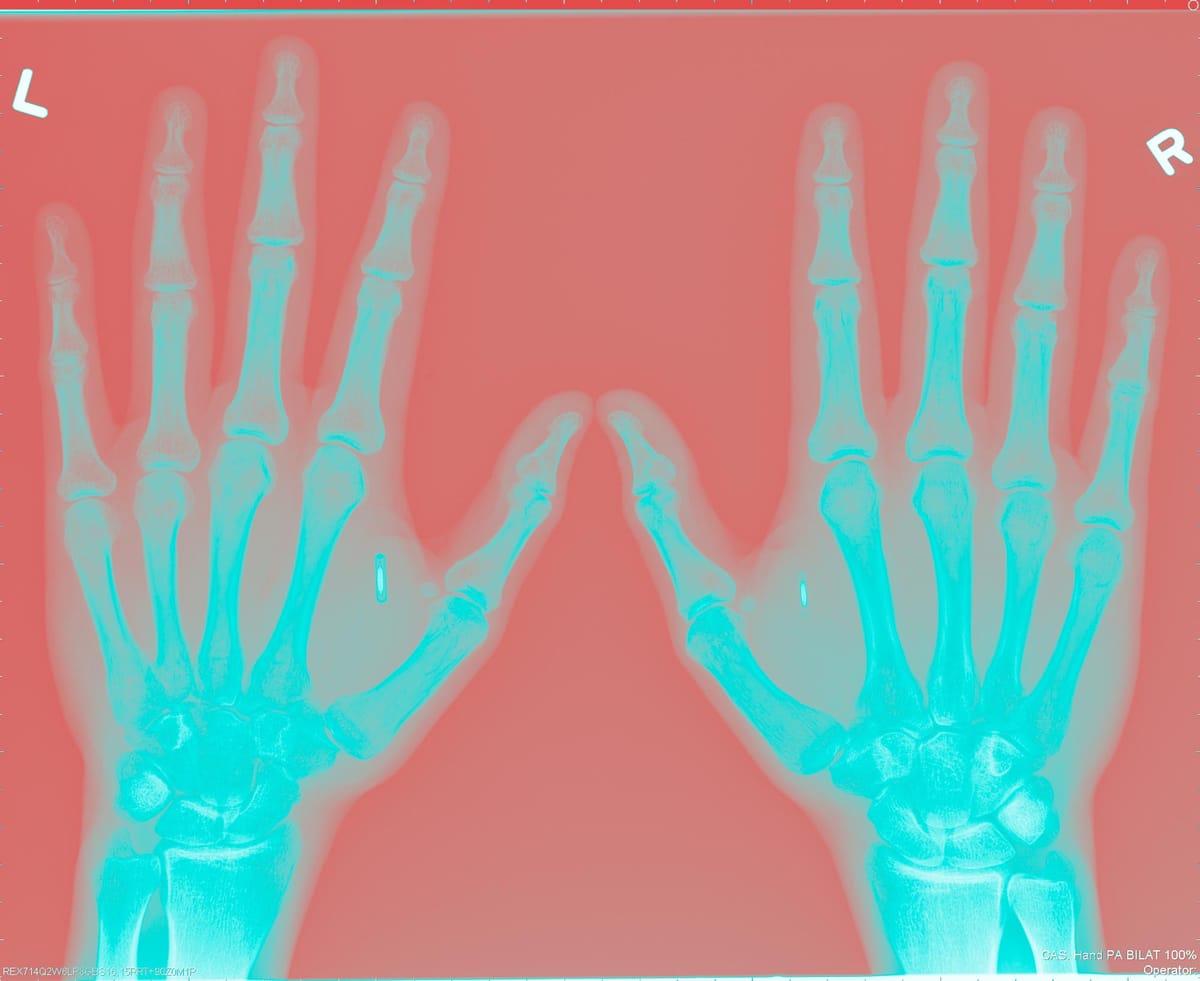

in copertina: radiografia delle mani di Amal Graafstra

Dieci anni e un altro impianto (nell’altra mano) dopo, Graafstra è fondatore di una start up che vende chip come i suoi — Dangerous Things, cose pericolose.